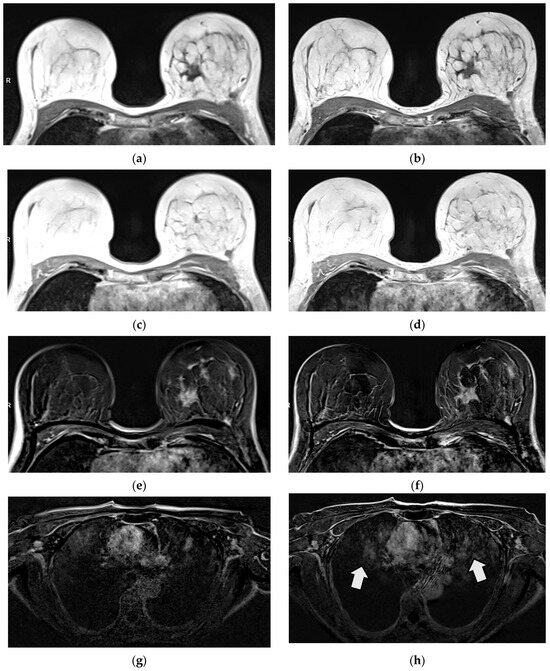

3.2.1. Qualitative Image Evaluation for T1w VIBE Pre-Contrast

3.2.2. Qualitative Image Evaluation for T1w VIBE Post-Contrast

3.3. Qualitative Image Evaluation for Post-Contrast Subtraction Images (SUB)